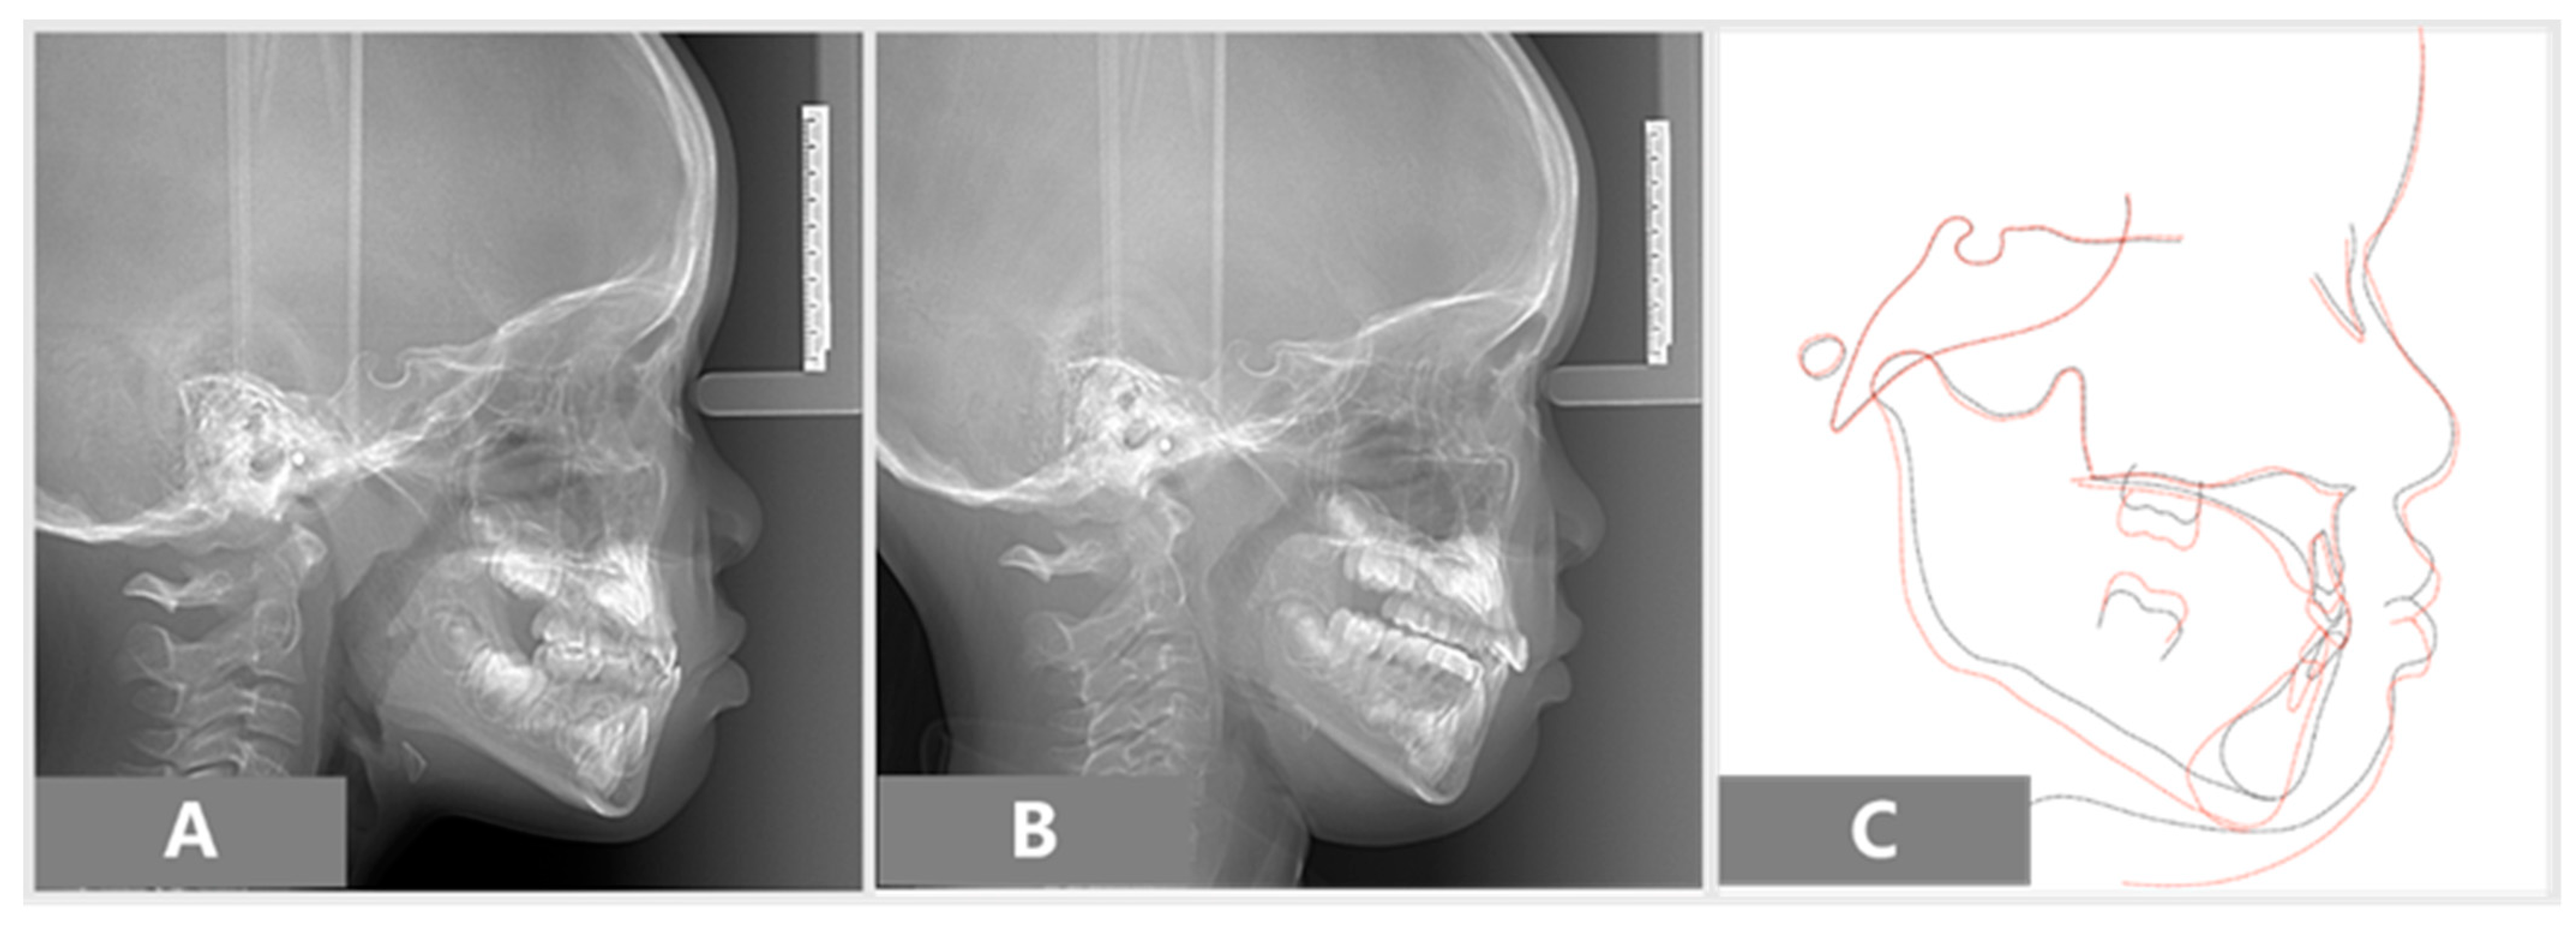

2.2. Assessments

3. Results

| Angular/Linear Measurement | Mean (6 Years) | Initial | Final |

|---|---|---|---|

| SNA (°) | 81–83 | 82 | 82 |

| SNB (°) | 79–81 | 82 | 79 |

| ANB (°) | 2–4 | 0 | 3 |

| Wits Appraisal (mm) | 0–1 | −4.5 | −4 |

| FMA (°) | 22–28 | 23.6 | 30 |

| IMPA (°) | 87–89 | 88 | 81 |

| U1 to NA (mm) | 21–23 | 15 | 24 |

| L1 to NB (mm) | 24–26 | 20 | 16 |

| NSAr (saddle angle) (°) | 118–126 | 128 | 128 |

| Gonial angle (°) | 129.8 | 146 | 135 |

| NSGn (°) | 59.8 | 67 | 67 |

| Y-axis (°) | 53–66 | 61 | 66 |

| Nasion perpendicular to point A (mm) | 0–1.0 | −2.7 | −3.6 |

| Upper pharyngeal space (mm) | 15–20 | 6.4 | 6 |

| Lower pharyngeal space (mm) | 11–14 | 12.7 | 11.8 |